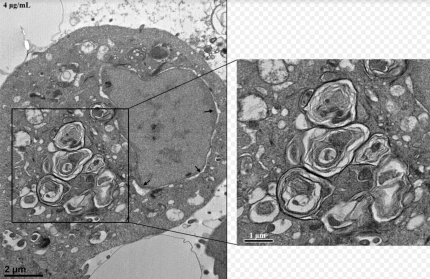

이 DDAC를 연구한 결과 4μg/mL의 농도에서

세포 생존율을 급격히 감소시키고

세포 내 소기관 손상과 함께

세포 자살과 세포막 손상을 유도한다고 하는데

정말 독한 물질임을 알 수 있는 대목이었습니다...

그리고 이 DDAC에 노출된 쥐와 세포에서는

라멜라 구조체가 형성되었고 이온을 함유하는

용액 내에서 그 구조가 뚜렷이 변화됐다고 합니다.